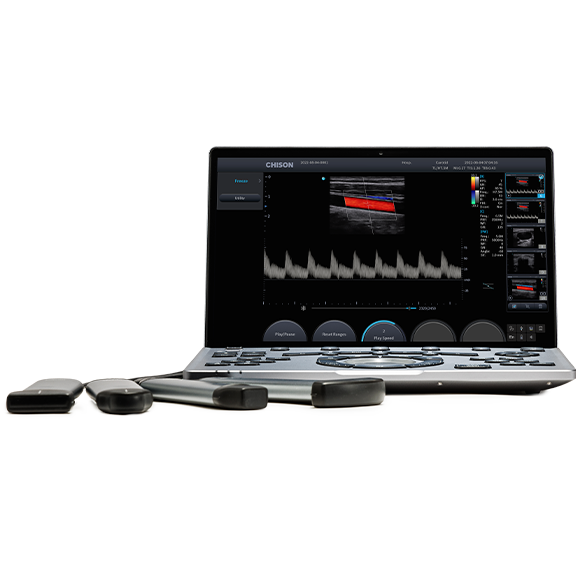

Lighter, Smarter and Faster

√ The world's lightest and thinnest laptop ultrasound.

√ Powered by brand new Air platform.

√ The intelligent design will bring an impressive user experience.

· Latest AIR platform

· 2.1 kg Ultra-light weight(with battery)

· 26 mm Thickness

· Spacious responsive touchscreen

· Easy connect with maximum 4 ports

· 180+mins for sanning & 36h+ for stand by

· Touch ID

The most innovative portable ultrasound CHISON SonoAir combines high-definition image quality and intelligent features to help physicians achieve a fast and reliable diagnosis. SonoAir offers a comprehensive ultrasound solution with its comfortable and intuitive user experience for your daily point-of-care exams.

· The lightest and thinnest touch-based laptop ultrasound to meet fast-changing environment.

· Get away from complex workflows with smart tools designed with ergonomics in mind.

· Made for diverse applications in the point-of-care area. More possibilities for you to choose.

Product Overview

CHISON SonoAir is designed to help doctors achieve higher outcomes and meet the growing demands in today's healthcare environment. Its excellent image performance and smooth workflow can save precious time with a more accurate assessment for both doctors and their patients.